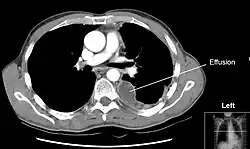

Imaging

A pleural effusion appears as an area of whiteness on a standard posteroanterior chest X-ray.[9] Normally, the space between the visceral pleura and the parietal pleura cannot be seen. A pleural effusion infiltrates the space between these layers. Because the pleural effusion has a density similar to water, it can be seen on radiographs. Since the effusion has greater density than the rest of the lung, it gravitates towards the lower portions of the pleural cavity. The pleural effusion behaves according to basic fluid dynamics, conforming to the shape of pleural space, which is determined by the lung and chest wall. If the pleural space contains both air and fluid, then an air-fluid level that is horizontal will be present, instead of conforming to the lung space.[10] Chest radiographs in the lateral decubitus position (with the patient lying on the side of the pleural effusion) are more sensitive and can detect as little as 50 mL of fluid. At least 300 mL of fluid must be present before upright chest X-rays can detect a pleural effusion (e.g., blunted costophrenic angles).

Chest computed tomography is more accurate for diagnosis and may be obtained to better characterize the presence, size, and characteristics of a pleural effusion. Lung ultrasound, nearly as accurate as CT and more accurate than chest X-ray, is increasingly being used at the point of care to diagnose pleural effusions, with the advantage that it is a safe, dynamic, and repeatable imaging modality.[11] To increase diagnostic accuracy of detection of pleural effusion sonographically, markers such as boomerang and VIP signs can be utilized.[12]